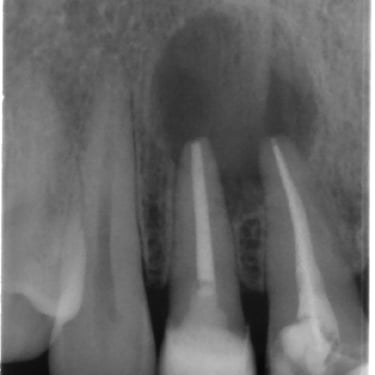

Calcificación Pulpar

La calcificación pulpar es la formación de depósitos de calcio dentro de la pulpa dental, que puede dificultar el tratamiento de conducto.

Los pacientes generalmente no tienen síntomas, pero pueden experimentar sensibilidad.

El tratamiento incluye la eliminación de los depósitos durante el tratamiento de conducto. Es importante tratarlo para evitar complicaciones durante el procedimiento.